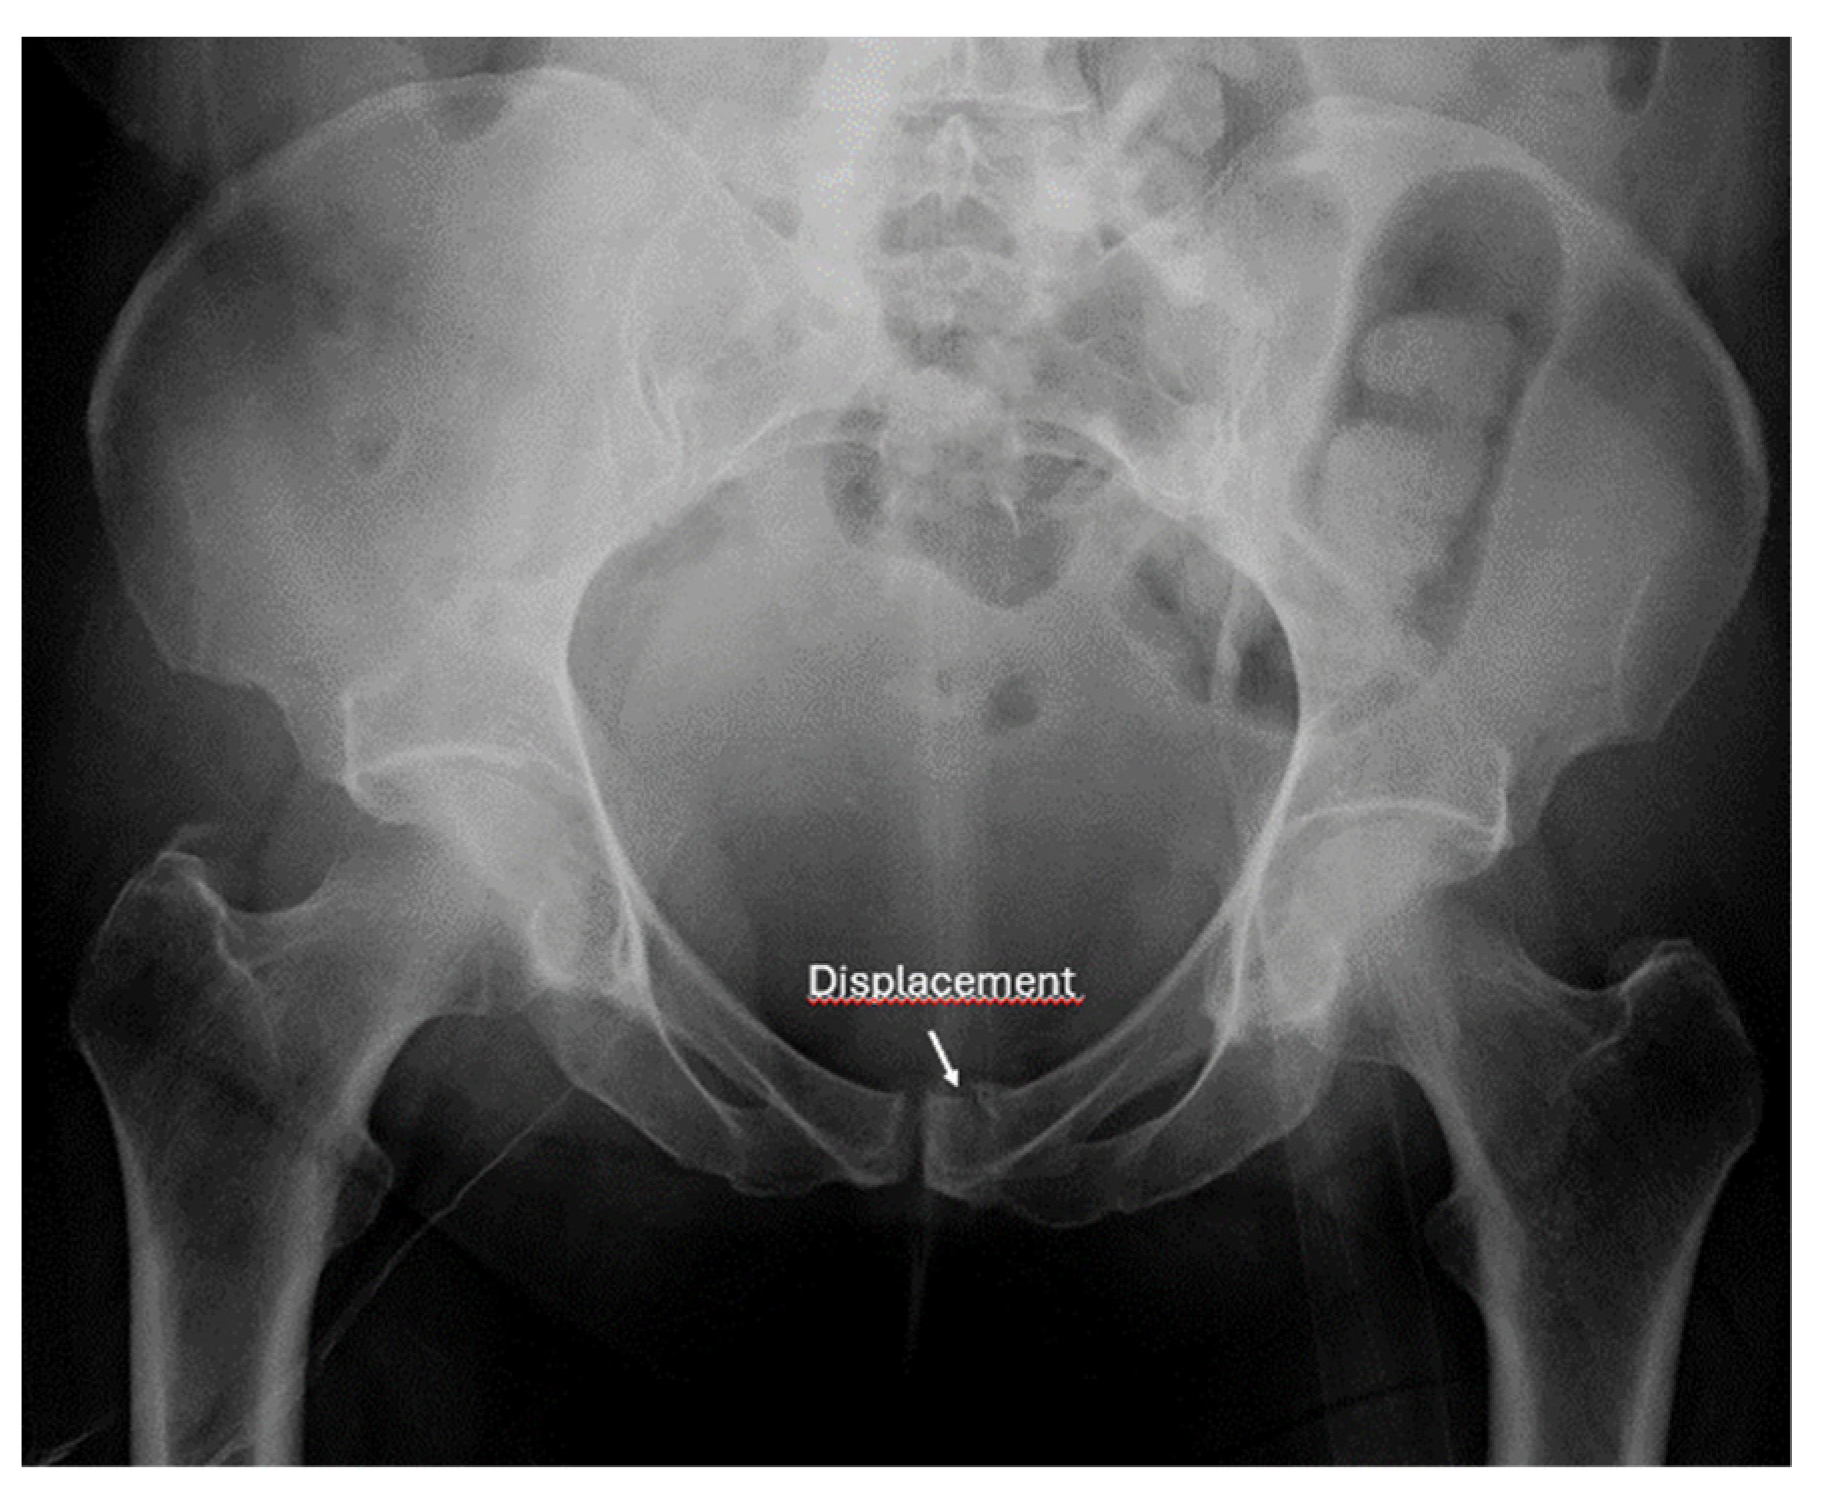

- Screening for fractures and hematoma during the primary survey in Advanced Trauma Life Support (ATLS), particularly in polytrauma patients, ultrasound enables rapid identification of fractures that are associated with life-threatening hemorrhage (e.g., pelvic or femoral fractures).

- Detection of instability signs in pelvic and spinal fractures: this is an emerging application where ultrasound can be used to assess dynamic instability or progressive displacement of fractures.

- Screening of fractures in the primary ATLS (Advanced Trauma Life Support) survey that are associated with or may cause life-threatening bleeding in polytrauma

- Recommendation 4: The E-FAST protocol, indicated for severely injured patients in shock, should be expanded to include fracture screening of long tubular bones and open-book fractures when the torso scan is negative for free fluid. This could identify hidden injuries and bleeding.

- In E-FAST, which is indicated for moderately to severely injured patients with shock, it can be expanded to fracture screening of long tubular bones and open-book fractures if the result of the torso scan is negative for free fluid.

- Ianniello, S.; Conte, P.; Di Serafino, M.; Miele, V.; Trinci, M.; Vallone, G.; Galluzzo, M. Diagnostic accuracy of pubic symphysis ultrasound in the detection of un-stable pelvis in polytrauma patients during e-FAST: The value of FAST-PLUS protocol. A preliminary experience. J. Ultrasound 2021, 24, 423–428. [Google Scholar] [CrossRef]

- Zhang, B.-F.; Lei, J.-L.; Zhang, H.; Wang, P.-F.; Wang, H.; Cong, Y.-X.; Huang, H.; Zhuang, Y. Use of ultrasonography for evaluation of stability of lateral compression type 1 (LC-1) pelvic fractures to assist determination of treatment strategy. J. Orthop. Surg. Res. 2019, 14, 7. [Google Scholar] [CrossRef]

- Zhang, B.-F.; Zhang, H.; Wang, P.-F.; Wang, H.; Lei, J.-L.; Fu, Y.-H.; Cong, Y.-X.; Huang, H.; Huo, X.-M.; Zhuang, Y.; et al. The role of ultrasonography in examination of the stability of Tile-B2 pelvic fractures: 7 case reports and a literature review. Med. (Baltim.) 2017, 96, e8100. [Google Scholar] [CrossRef]